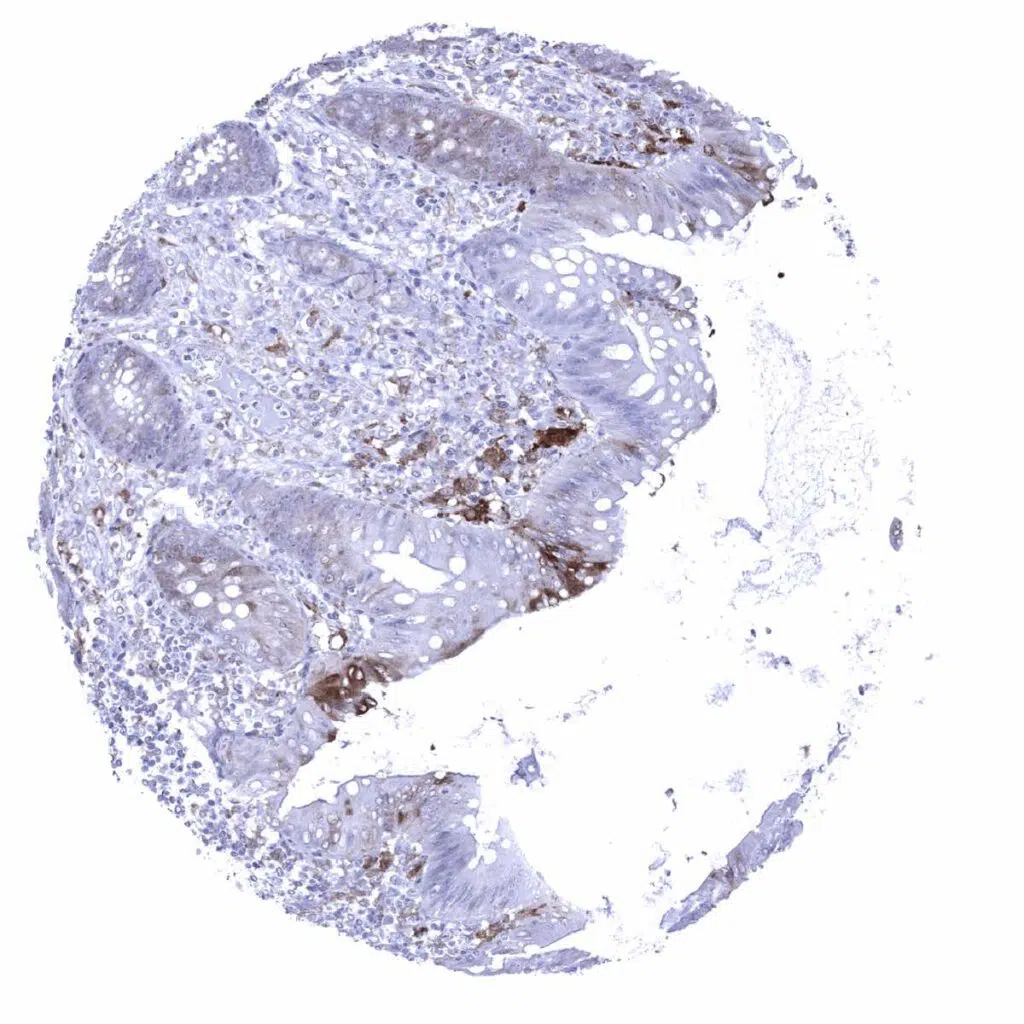

Lymph node – GS staining of weak to moderate intensity occurs in sinus macrophages, dendritic cells, and in endothelial cells of small capillaries

Lymph node – Strong GS staining of dendritic cells in a germinal centre